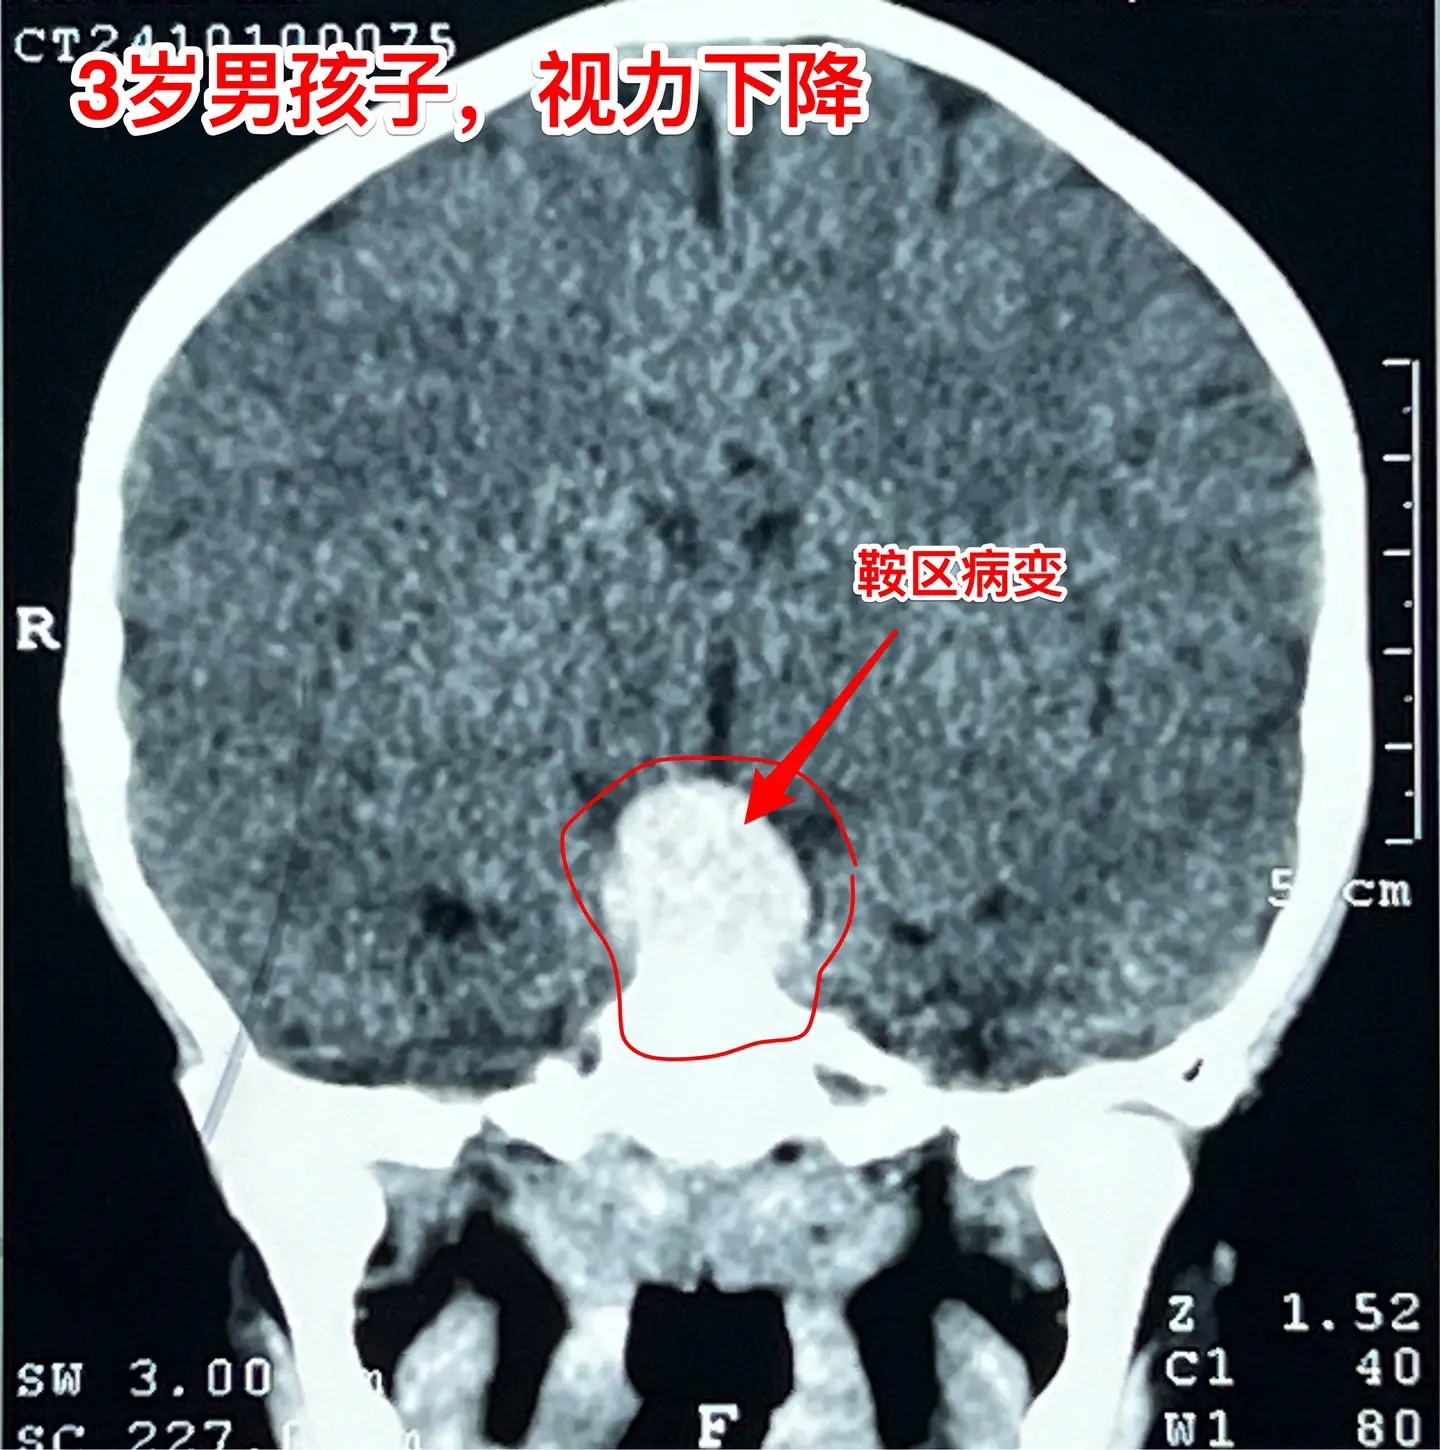

鞍区高密度囊肿-高密度不等于钙化。拉克氏囊肿在CT扫描中大多数呈低密度影,少数呈现比较均匀的高密度影,但是绝对不是钙化。不能误认为是颅咽管瘤。 三岁男孩子因偶然原因行CT扫描发现鞍区病变。测视力才发现患儿的视力有下降(0.3)。根据CT、磁共振可以判断这是拉克氏囊肿,病变没有钙化。 拉克氏囊肿如果压迫视神经、视交叉造成视力下降或者视野缺损,则有手术指征。 今日10.25经翼点入路将病变切除。术中快速冰冻报告为拉克氏囊肿。